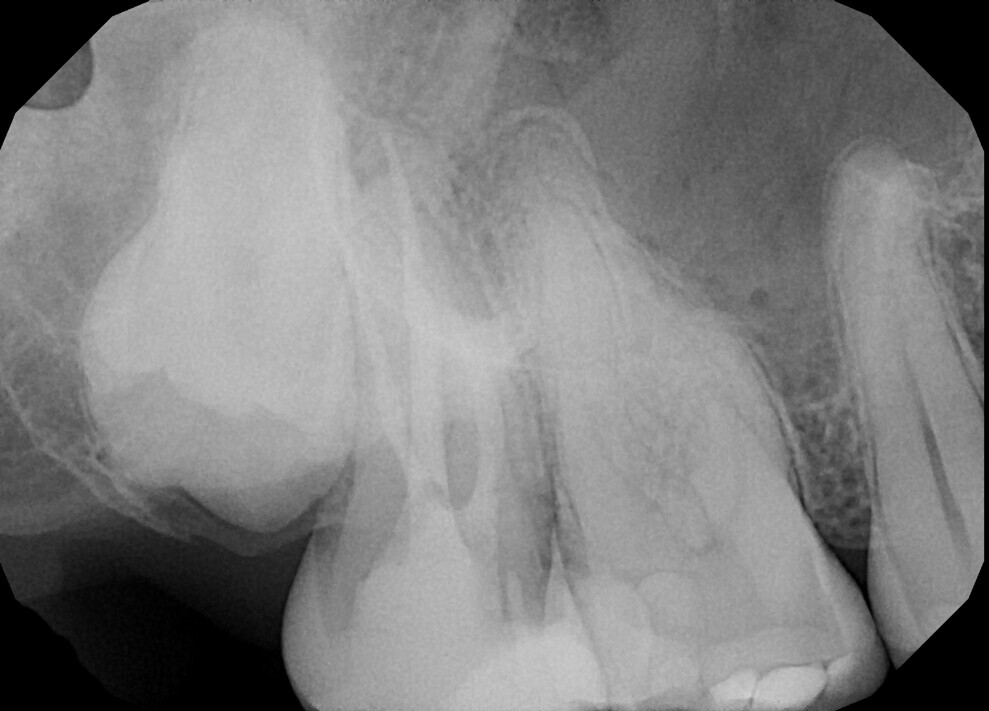

Fig.: 2

Most technical instructions advise dental practitioners to use files in three to four continuous pecking motions, every move advancing a little bit more without removing the file, and then to remove the file from the canal, clean the instrument, irrigate the canal and repeat, until the operator reaches the apical area. This kind of approach creates a pumping motion and pushes all the debris laterally and towards the apical area, respectively. Then the final irrigation protocol is performed. It is much more difficult from the beginning because of all the blockages in the lateral anatomies and ramifications created with the preparation (Fig. 2).